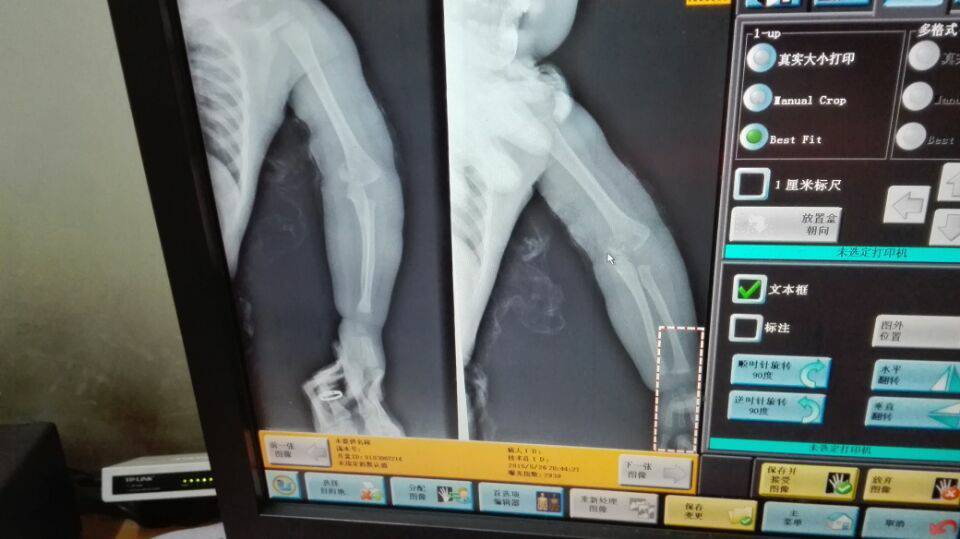

请骨科专家看看,一岁3个月男孩,左手手肘骨折,通过中医复位的方法一个多星期了,但是一直不好拍片复查,担心骨折端钙化或者坏死,医生都劝早日做手术为好,请问需要动手术吗,还是继续保守治疗,急急急,感谢好人

你是找正规医院的中医复位的吗?看你这片子没有复上啊,尺骨的位置根本不对,桡骨小头也有半脱位的禁菠征象。另外,小孩子的关节脱位、骨折一般是不建以阶议术后的,因为考虑会伤及骨骺,另外小孩子长得也快、伤好后助旧裁塑性也快,但是这是在复位达到要求的情况下。